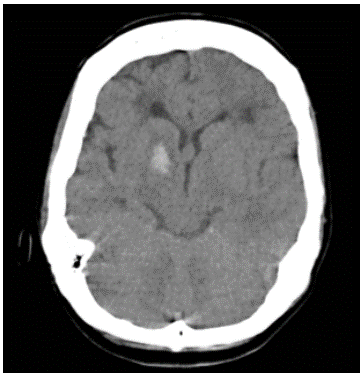

Paciente femenina de 45 años de edad de etnia mestiza sin antecedentes patológicos, quien ingresa al servicio de urgencias de un hospital de cuarto nivel de la ciudad de Cartagena (Bolívar) el día 1° de julio de 2019 con cuadro clínico de una semana de evolución consistente en cefalea holocraneana, de moderada intensidad, con posterior aparición de un episodio convulsivo tonicoclónico generalizado, con relajación de esfínteres, sin especificarse la duración de la crisis. Al ingreso al servicio de urgencias tensión arterial de 140/90 y restantes signos vitales normales sin déficit neurológico focal. Se realizó una tomografía de cráneo simple evidenciando foco hemorrágico intraparenquimatoso de localización gangliobasal derecho, leve enfermedad multifocal isquémica de pequeños vasos, foco malásico occipital derecho y evento isquémico antiguo frontal izquierdo adyacente al ventrículo lateral izquierdo (Figura 1). En los paraclínicos iniciales no se encontró alteración en la analítica sanguínea con reporte de hemoleucograma y recuento de plaquetas normales, azoados, ionograma y tiempos de coagulación dentro de límites de normalidad. Se realizó panangiografía cerebral encontrando como hallazgos: adelgazamiento de arterias carótidas internas y de cerebrales posteriores (observable esto último en el 50% de los casos) con presencia de neovascularización anormal a nivel de núcleos de la base, compatible con enfermedad de Moyamoya (Figura 2). Con estos resultados se evaluó en junta médica de neurocirugía la conducta a seguir, considerando que se puede beneficiar de manejo endovascular; sin embargo, ante el alto riesgo de recurrencia del sangrado, se postergó la realización del mismo al menos cuatro semanas.

Figura 1 TC de cráneo sin contraste. Corte axial que evidencia hipodensidad nucleobasal derecha sugestivo de sangrado.

En nuestro caso la enfermedad de Moyamoya se presentó como un primer episodio convulsivo generalizado con posterior recuperación, sin un aparente déficit motor o cognitivo derivado de una hemorragia intraparenquimatosa nucleobasal derecha detectada por tomografía de cráneo simple, hallazgo que corresponde con la literatura, la cual menciona que la hemorragia intraparenquimales más común que sus formas intraventricular o subaracnoidea en pacientes con esta enfermedad y que las localizaciones más frecuentes son los núcleos de la base, el lóbulo temporal medial y el tálamo 1,4. Entre las posibles causas de la hemorragia en pacientes con enfermedad de Moyamoya destacan la ruptura de alguna de las colaterales frágiles y/o de algún aneurisma formado por las alteraciones en el flujo cerebral (zonas de altas y bajas presiones que se forman durante la enfermedad). Los sitios más comunes de formación de estos aneurismas son en la parte terminal de la arteria basilar y en la arteria comunicante posterior. La ubicación de la hemorragia en nuestro caso planteó el diagnóstico diferencial con la ruptura aneurismática y la asociada a una malformación arteriovenosa.